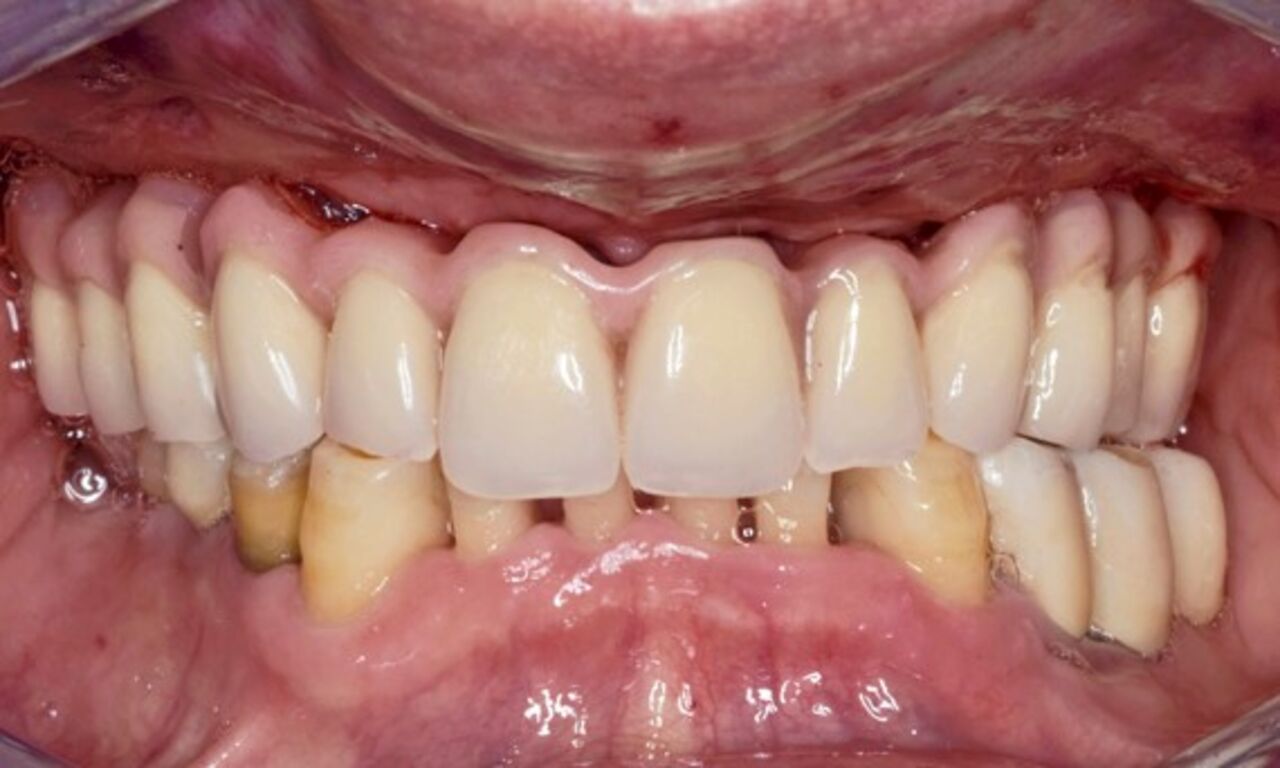

Langfristiger Knochenerhalt

Lassen Sie sich von unserer Erfolgsbilanz inspirieren: Wir haben den Standard in puncto Knochenerhalt gesetzt. Aufbauend auf dem bewährten Renommee des Astra Tech Imlant Systems für eine schnelle, vorhersagbare Osseointegration. Die OsseoSpeed-Oberfläche beitet langfristigen Knochenerhalt und übertrifft zwei andere Implantat-Oberflächen in Bezug auf marginalen Knochenerhalt in 1-Jahres- und 5-Jahres-Follow-ups.*

Langfristiger Knochenerhalt und exzellente Ästhetik dokumentiert und klinisch erprobt.

Die Hauptmerkmale des Implantats – EV-Innenverbindung, OsseoSpeed, MicroThread, Soft Tissue Chamber – wurden für das Astra Tech Implant System hinsichtlich Knochenerhalt und Ästhetik dokumentiert und klinisch erprobt.